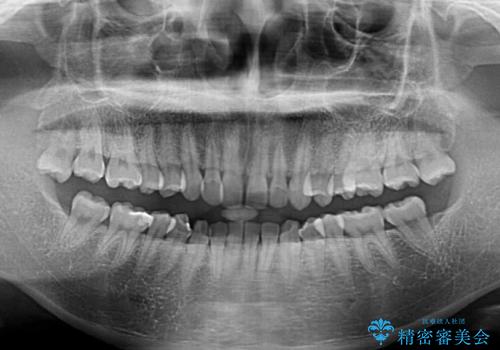

- 前歯の隙間やクロスバイトを気にして来院された患者様です。

結婚式の予定があり、可能であれば結婚式までに治療を終えたいとのことで、短期間で治療をおける可能性の高いワイヤー装置にて矯正治療を行うこととしました。